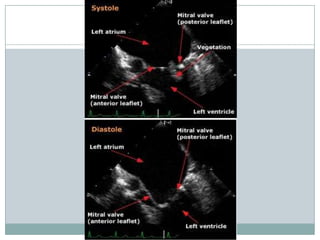

Diagnostic criteria for vegetations

** Valvular vegetation is defined as "a discrete mass of echogenic material adherent at

some point to a leaflet surface and distinct in character from the remainder of the

leaflet" based upon the following characteristics:

Texture — gray scale and reflectance of myocardium

Location — upstream side of the valve in the path of the jet or on prosthetic material

Characteristic motion — chaotic and orbiting; independent of valve motion

Shape — lobulated and amorphous

Accompanying abnormalities - abscess and pseudoaneurysm, fistulae, prosthetic

dehiscence, paravalvular leak, significant preexisting or new regurgitation

** Vegetations also characteristically prolapse into the upstream chamber: mitral

vegetations into the atrium in systole and aortic vegetations into the left ventricular

outflow tract during diastole.

**Vegetations tend to flank the regurgitant jet.